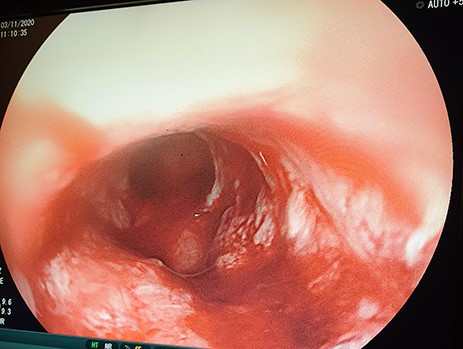

A 62-year-old male, a smoker and excessive alcohol consumer, non-hypertensive, presented with progressive grade-6 dysphagia that started gradually 7-month ago, associated with unintentional loss of weight. His biological brother was diagnosed with oesophageal cancer 3-year back and had an improvised GFT inserted but passed away shortly thereafter. On general examination he was weak, cachexic, severely pale, not jaundiced, not cyanosed with bilateral pitting lower limb edema with vitals within normal range. Full blood picture initially showed microcytic hypochromic anaemia of 6.4 g/dl, other parameters were essentially normal. Chest X-ray and abdominal ultrasound were essentially normal. Patient did an OGD which revealed at 20 cm a fungating mass partially obstructing lumen (Fig. 4), a biopsy was taken but the scope could not pass through. Histology results for biopsy showed oesophageal invasive squamous cell carcinoma grade 2.

OGD showing a fungating mass partially obstructing esophageal lumen.